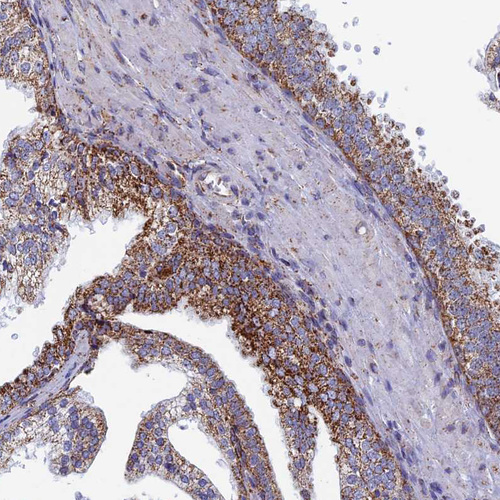

Immunohistochemical staining of human rectum shows strong granular cytoplasmic positivity in glandular cells.